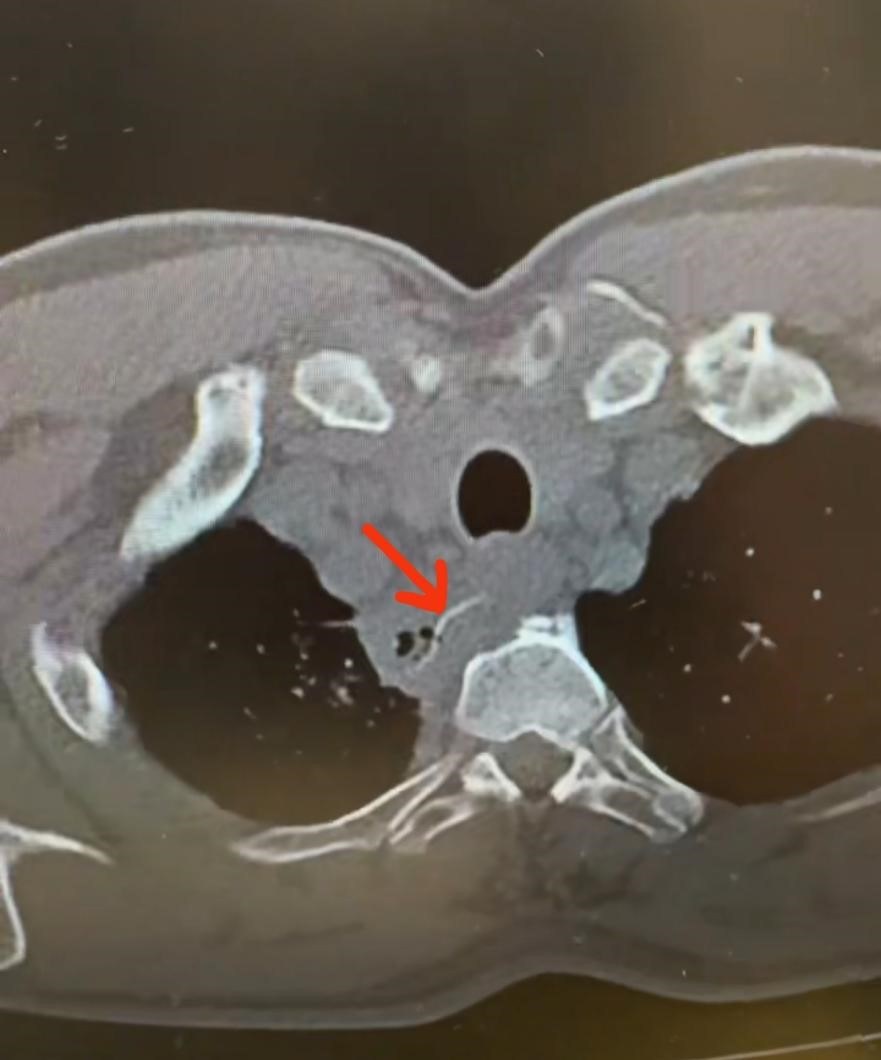

急诊医学科医生迅速为胡先生安排了胸部CT检查,影像结果令人心惊:右肺上叶气管旁软组织影伴约3cm细条状高密度影,右肺上叶模糊斑片影,高度怀疑是异物穿孔并发感染。当医生询问近期是否有被异物卡喉的经历时,胡先生这才猛然想起 ——一周前就餐时,他曾被一根细小的鱼刺卡到喉咙。

“当时觉得没什么大不了,吞了口饭就没感觉了。”胡先生懊悔地说。正是这个看似平常的举动,让这根鱼刺开启了危险的体内“游走”:它穿透食管壁后,部分扎入右上肺组织,引发了严重的肺部感染,更可怕的是,CT 显示异物距离胸主动脉仅毫厘之遥,随时可能刺破血管导致致命性大出血。

胡先生的胸部CT影像,红色箭头所示为异物 医院供图

手术室迅速做好准备,全麻状态下,手术团队通过胸腔镜探查发现,食管上段近胸廓入口处有一长约3cm,宽2mm针形鱼刺,破出食管,部分扎入右上肺,引起右肺部分组织感染,右侧胸壁内大量粘连,所幸没有活动性出血。